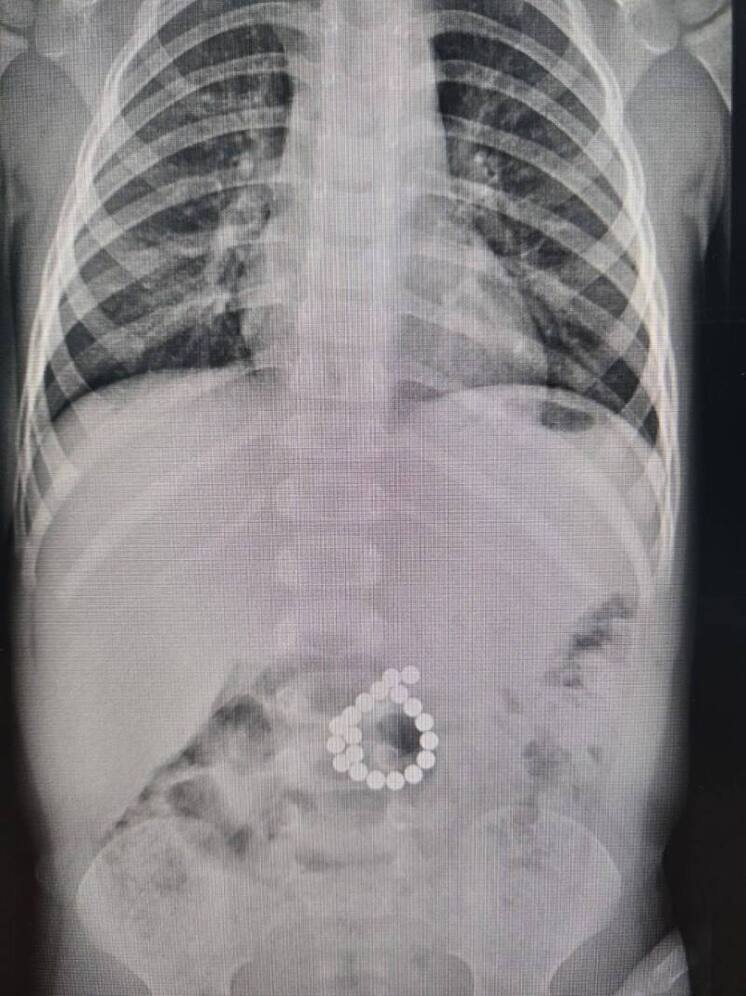

В Центр охраны материнства и детства доставили мальчика двух лет семи месяцев. У ребёнка наблюдалась высокая температура и сильные боли в животе. Врачи выяснили, что несколькими днями ранее малыш играл с магнитным конструктором и проглотил несколько деталей.

Ситуация оказалась критической: оказавшись в кишечнике, магниты начали притягиваться друг к другу через стенки органа. Это привело к сдавлению тканей и двойной перфорации кишечника — опасному состоянию, которое может вызвать тяжёлое воспаление и другие серьёзные осложнения.

Ребёнку немедленно провели хирургическую операцию. Врачи обнаружили в толстой кишке 19 магнитных элементов, успешно удалили их и ушили повреждённые участки кишечника.